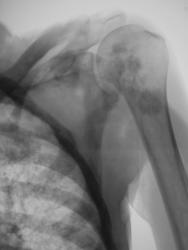

Диссеминированный туберкулёз лёгких.

Милиарная диссеминация, преимущественно в средних и нижних отделах.

Случай представлен доктором Коробейниковым.